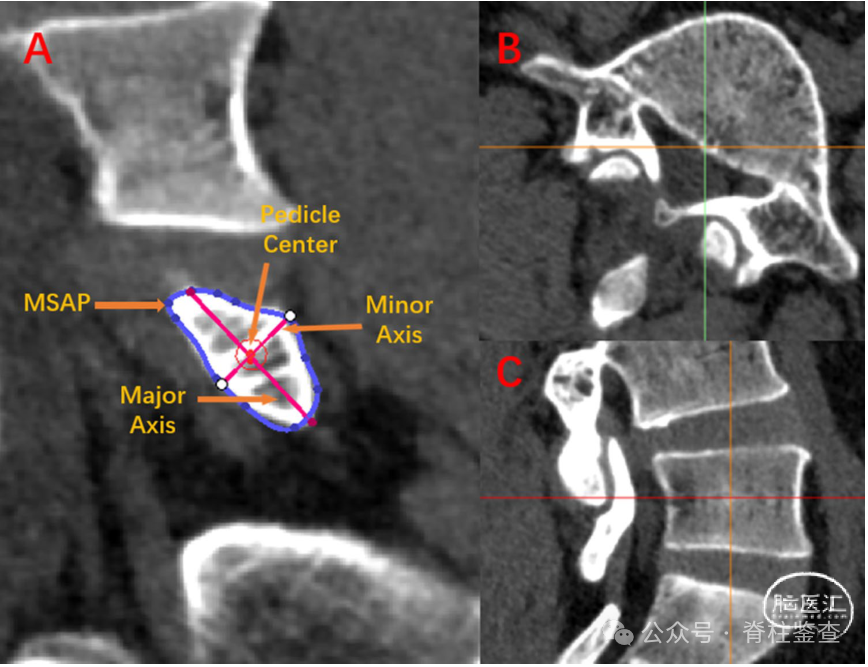

不同类型L5椎管的TD差异有统计学意义,圆型L5椎管Magerl点位于外侧且相对于最佳入口点偏差<1 mm的病例较多,三叶型L5椎管相对于最佳入口点Magerl点位于内侧的病例较多。

在不同的椎管类型L5中,Magerl点相对于最佳进入点的距离显著不同,并且在三叶型椎管L5中Magerl点相对于最佳进入点的距离大于在圆型渠道L5中的距离。